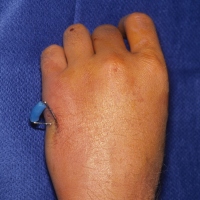

| Appearance at four

weeks. |